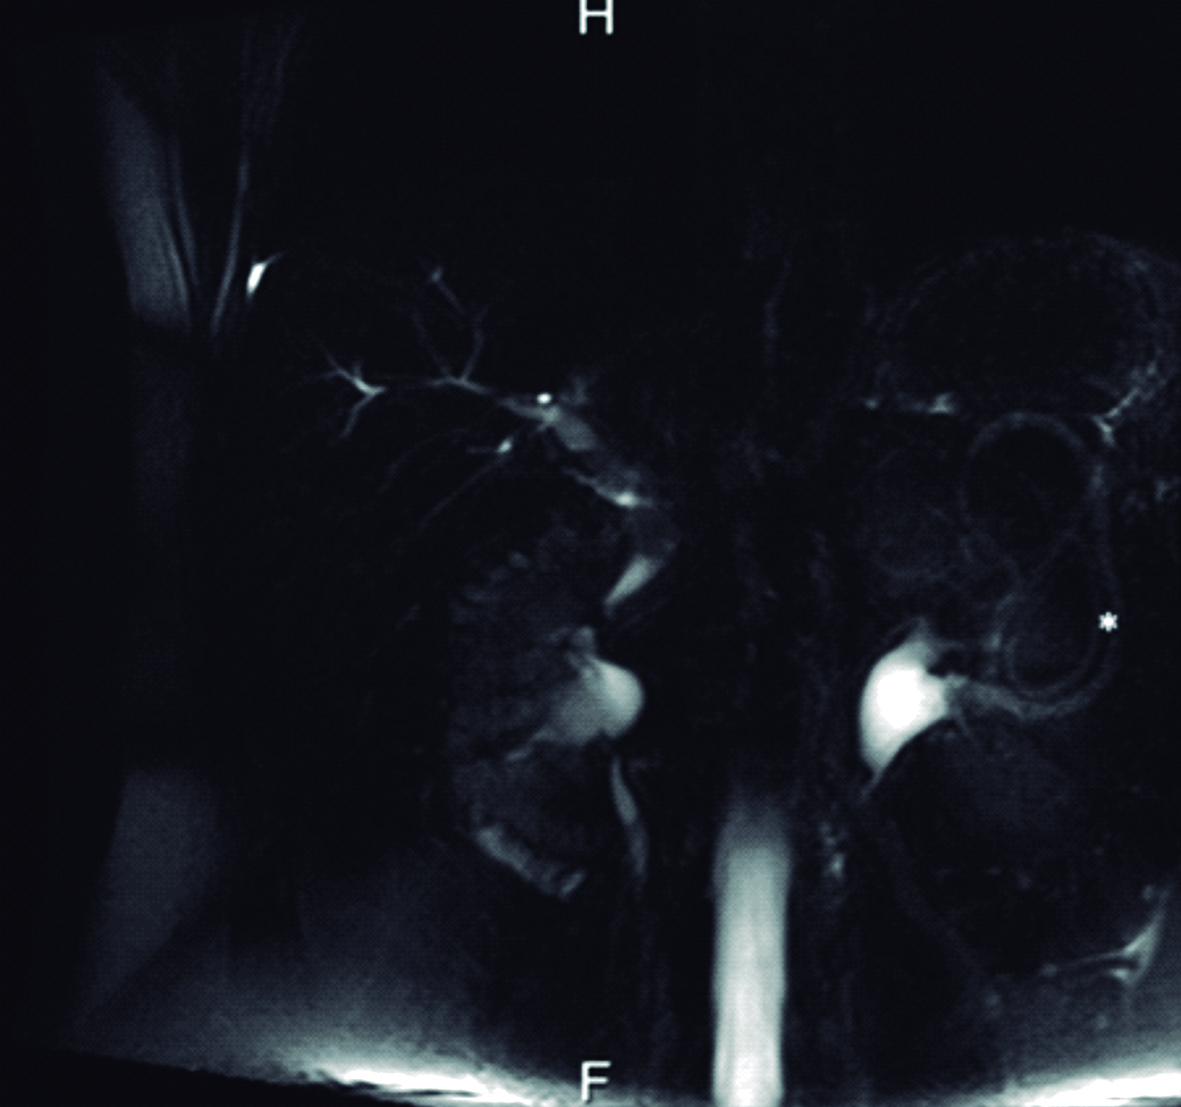

Se interroga a la paciente y refiere haber sido estudiada previamente con una colangiografía por resonancia magnética tres meses previo a la consulta en otro centro hospitalario. En ese momento la vía biliar principal no estaba ocupada. Retrospectivamente se identificaron los parásitos en el tubo digestivo proximal (Fig. 4 y 5).

Figura 4. Resonancia Magnética

a y b) Imágenes en plano coronal potenciadas en T2 sin saturación grasa. A nivel de asas yeyunales proximales se identifican los parásitos

como imágenes lineales ligeramente hiperintensas con un área central hipointensa (*).

La resonancia magnética es una excelente modalidad no invasiva para diagnosticar la presencia de parásitos en la vía biliar. En imágenes ponderadas en T1, los gusanos se ven como estructuras tubulares lineales ligeramente hiperintensas con un área central hipointensa y en la colangiografía por resonancia se visualizan como defectos lineales de relleno hipointensos en el tracto biliar. (4, 9, 10)